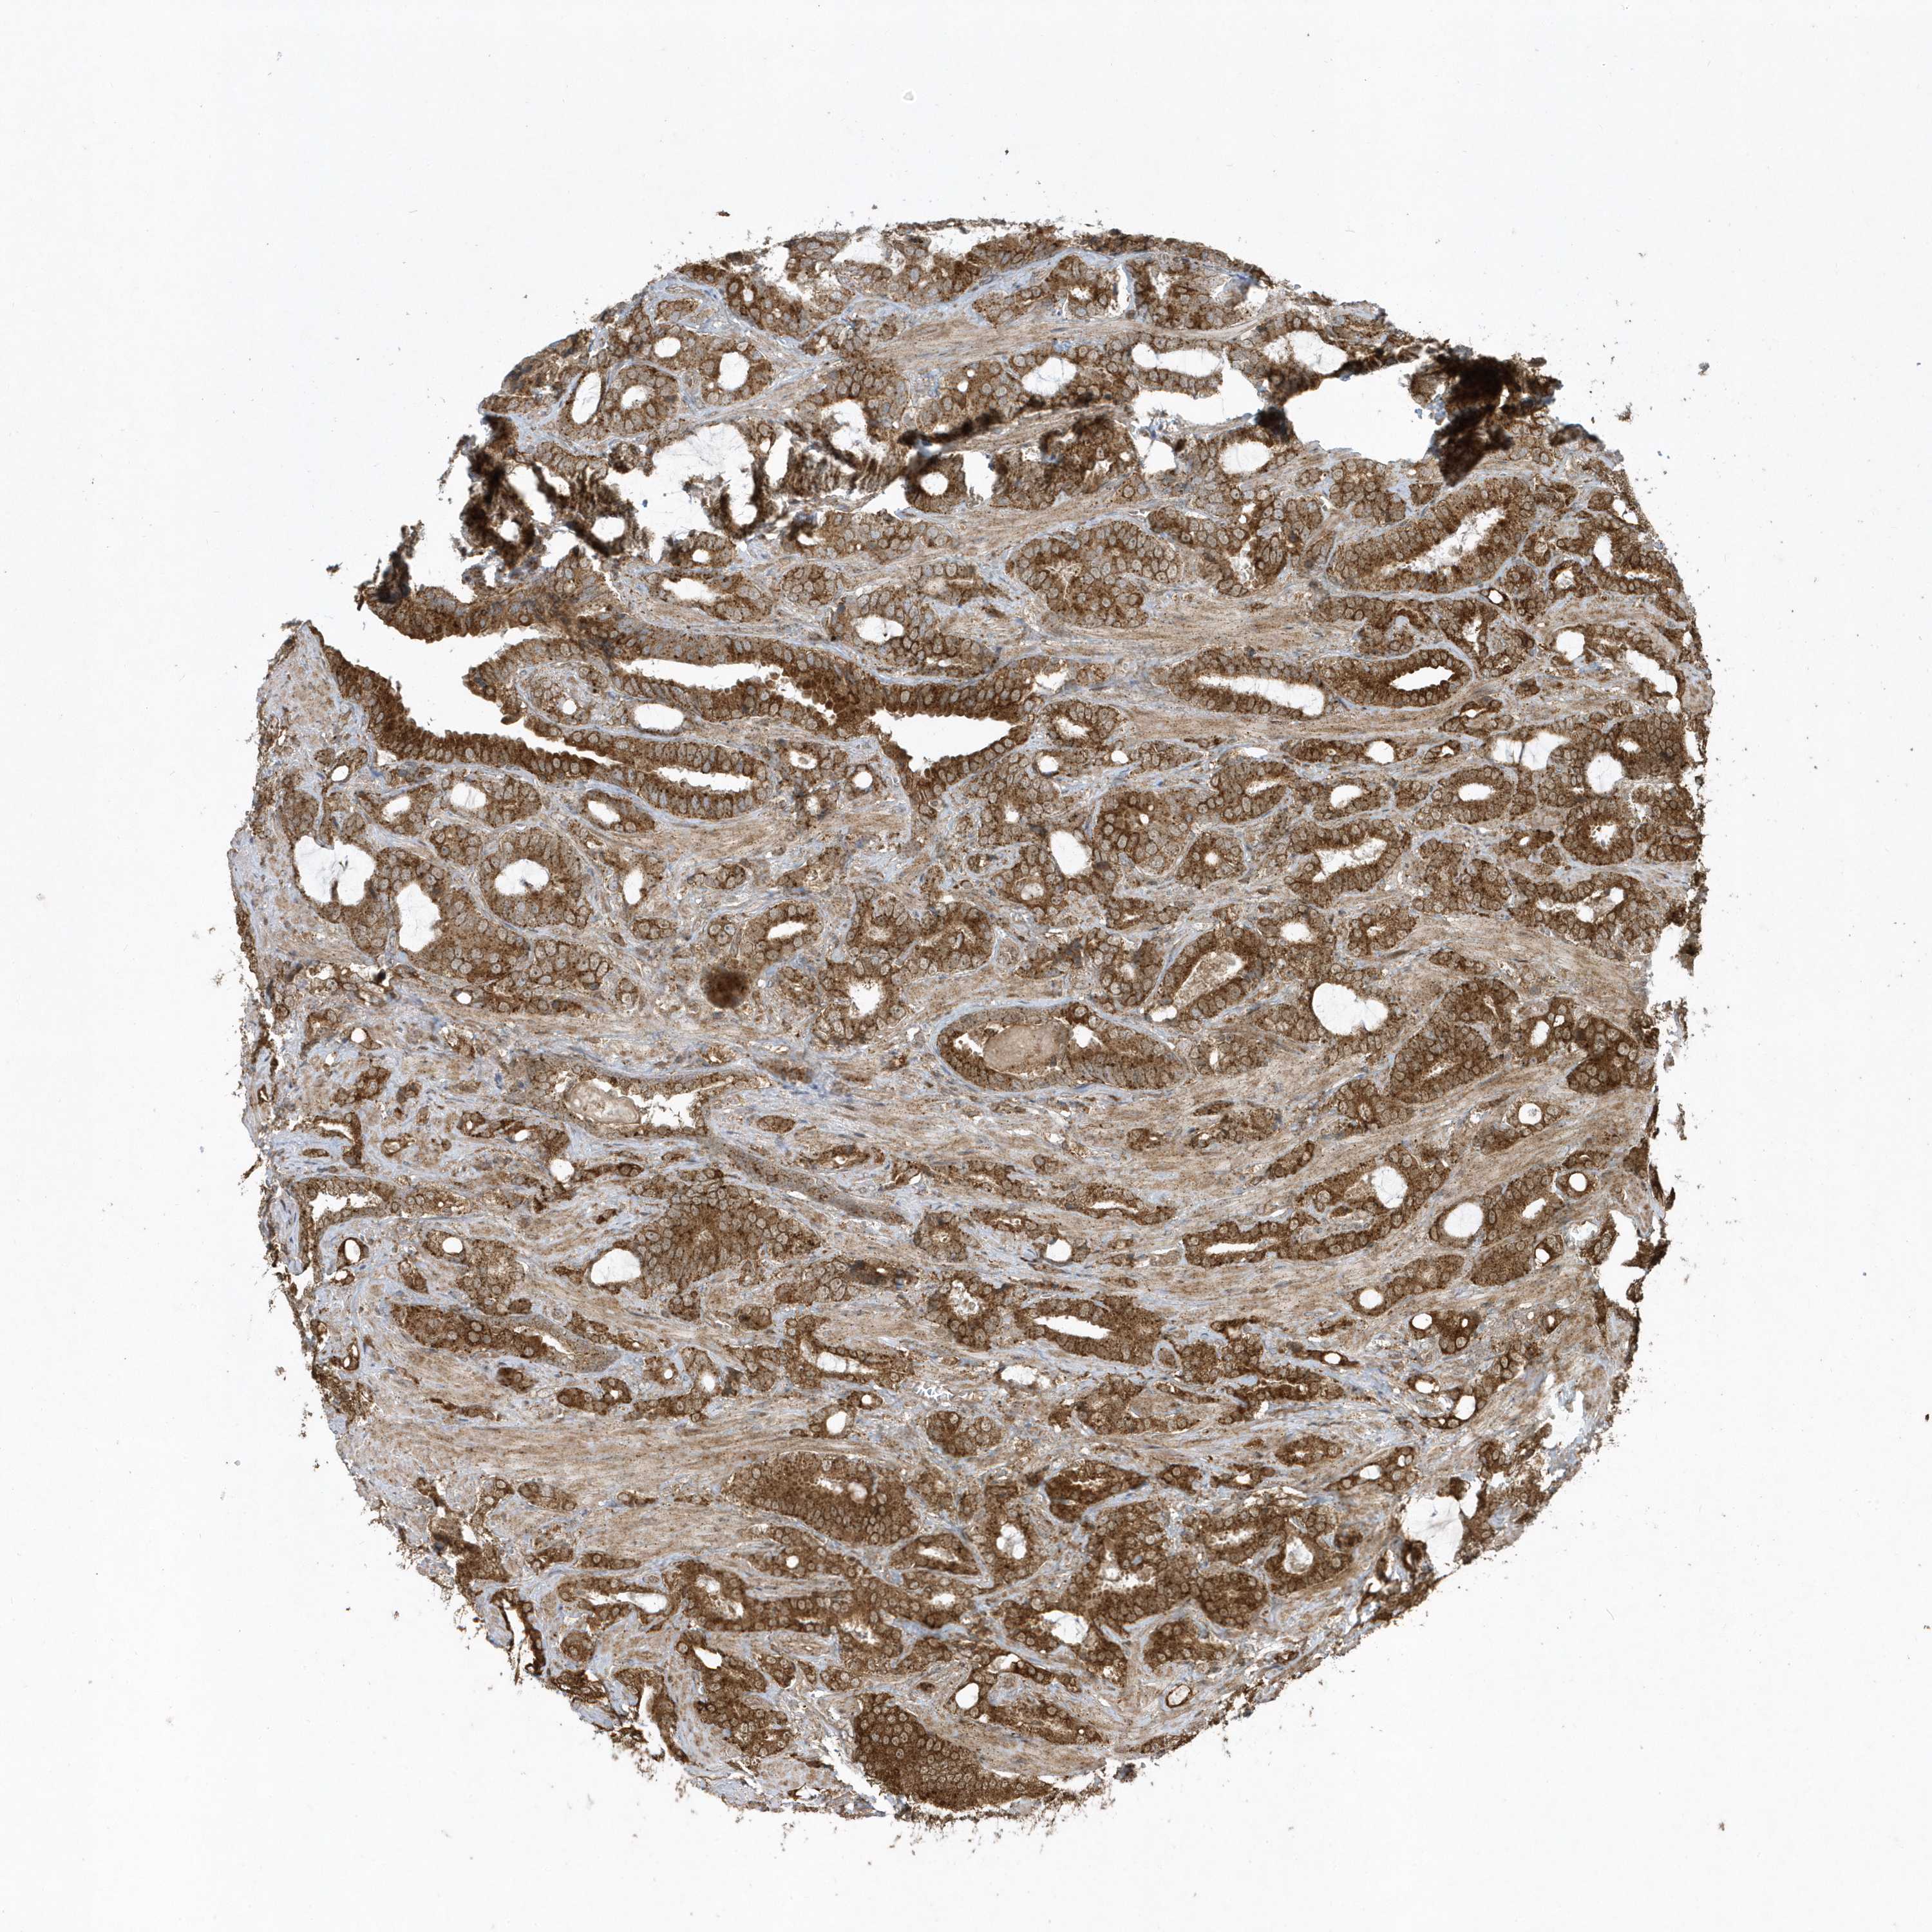

PROSTATE CANCER - Protein expressioni

A mouse-over function shows sample information and annotation data. Click on an image to view it in a full screen mode. Samples can be filtered based on level of antibody staining by selecting one or several of the following categories: high, medium, low and not detected. The assay and annotation is described here.

Note that samples used for immunohistochemistry by the Human Protein Atlas do not correspond to samples in the TCGA dataset.

Antibody stainingi

Antibody staining in the annotated cell types in the current human tissue is reported as not detected, low, medium, or high, based on conventional immunohistochemistry profiling in selected tissues. This score is based on the combination of the staining intensity and fraction of stained cells.

Each image is clickable and will lead to virtual microscopy that enables deeper exploration of all samples and also displays staining intensity scores, fraction scores and subcellular localization as well as patient and tissue information for each sample.

Antibody HPA035800

Staining

High

Medium

Low

Not detected

Intensity

Strong

Moderate

Weak

Negative

Quantity

>75%

75%-25%

<25%

None

Location

Nuclear

Cytoplasmic/membranous

Cytoplasmic/membranous,nuclear

Adenocarcinoma, High grade

Adenocarcinoma, Low grade